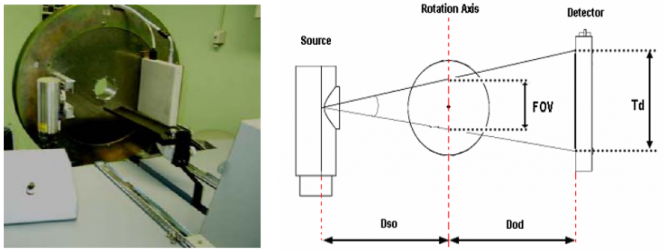

Diseño y desarrollo de un sistema micro-CT de alto rendimiento para pequeños animales de laboratorio

| JOURNAL | XXIV Congreso Anual de la Sociedad Española de Ingeniería Biomédica, Noviembre 2006 |

Se describe la implementación de un escáner micro-CT adecuado para ser utilizado como elemento complementario en

diferentes escáneres PET para pequeños animales. El diseño básico del sistema se basa en el montaje de un tubo micro-foco de rayos-X y un detector digital plano sobre un soporte rotatorio.

| JOURNAL | IEEE Nuclear Science Symposium Conference Record, 2006 |

We have developed an X-ray cone beam tomograph for in vivo small-animal imaging using a flat panel detector (CMOS technology with a columnar CsI scintillator plate) and a microfocus X-ray source in a geometric configuration with 1.6 magnification and 7.5 cm2 field of view. This work presents an initial characterization of this new system. We measured the detector modulation transfer function (MTF), detector stability, system resolution, the quality of the reconstructed tomographic images and radiated dose.

The goal of this work was the development of a low-cost micro-CT scanner, which could be used as an add-on in our previously developed PET systems for small-animals. The scanner design consists of a single-processor computer controlling a micro-focus X-ray tube and a flat panel detector, assembled in a common rotating gantry. The geometrical configuration was selected to achieve a spatial resolution of about 12 lp/mm with a field of view appropriate for small animals such as mice and rats. The radiated dose is controlled during the acquisition by two different elements: an aluminium filter and a tungsten shutter, attached to the X-ray source. The shutter is controlled by the computer in synchronism with the gantry rotation and the detector image integration.